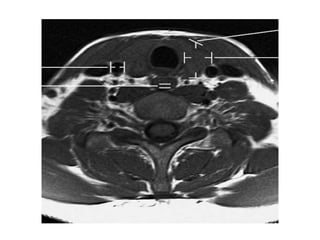

O documento fornece informações sobre como realizar exames de ressonância magnética do pescoço e angiorressonância magnética das carótidas, incluindo parâmetros, programação, anatomia, exames estruturais e funcionais, dicas e protocolos.